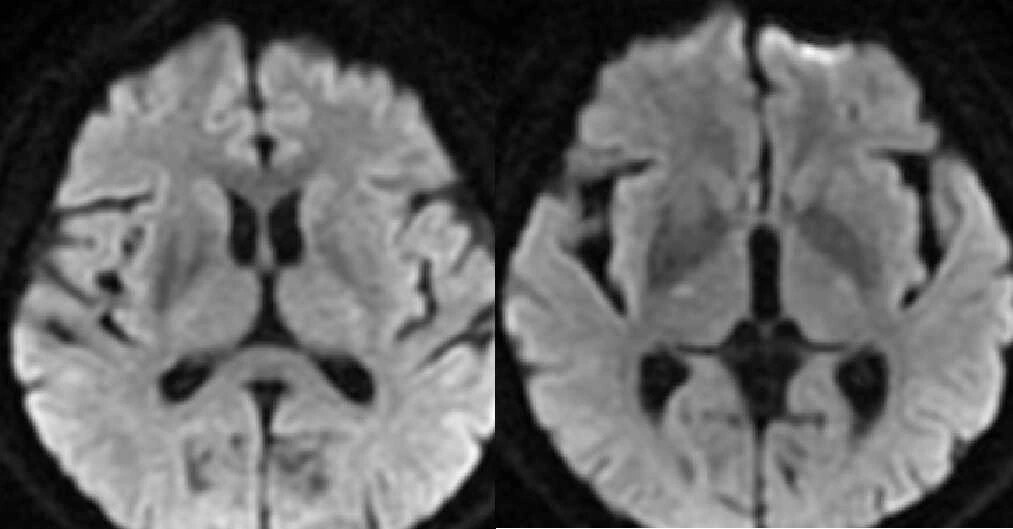

3 天后行 MRI 检查,图像如下:

T1WI 示病灶呈高信号,T2WI 呈低信号,DWI 信号不高,病灶边界清晰,无占位效应及周围水肿,内囊未累及。

影像表现为对侧纹状体(主要为壳核)的异常,CT 上表现为高密度,CT 值约 40-50 HU。T1WI 高信号为该病最主要的影像学特点,T2WI 信号表现各异,多呈低信号,少数呈高或混杂信号,不具有特征性。增强后病灶无强化。病灶边界清晰,无明显水肿及占位效应,不累及内囊。但也有部分病例无任何影像学改变。T1WI 高信号一般持续数月到数年不等,随着病情的好转可减弱甚至消失。